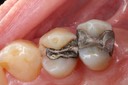

Joe Cha #3 amalgam removal